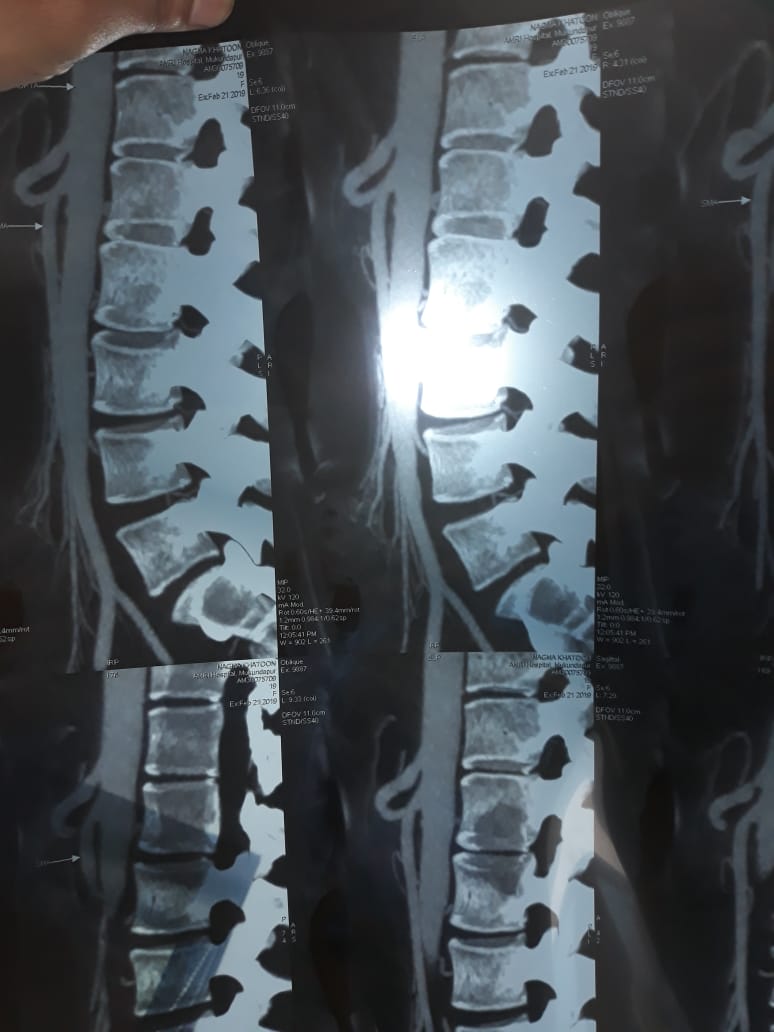

A Young lady who was a small kid...when her mother was operated for a Complex Gastrointestinal condition almost 14 years back by Dr Suddhasattwa Sen suddenly came in with severe blood loss from Gastrointestinal tract with a loss of almost 2 to 3 litres of blood with Shock with fainting . Further stabilisation was done and then extensive investigation revealed not only Piles and GI Ulcers but also SRUS Bleeding ulcers in rectum. A condition called Solitary Rectal Ulcer Syndrome ( a complex and difficult to cure anorectal problem ) . Her hemoglobin dropped to below 7 gm% She finally underwent surgery after 5 days and left home after 2 days post op without any further bleed or problems .